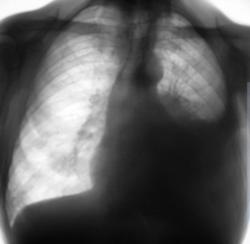

Субтотальное снижение прозрачности левого легочного поля без смещения средостения.

Субтотальное снижение прозрачности левого легочного поля со смещением средостения вправо.